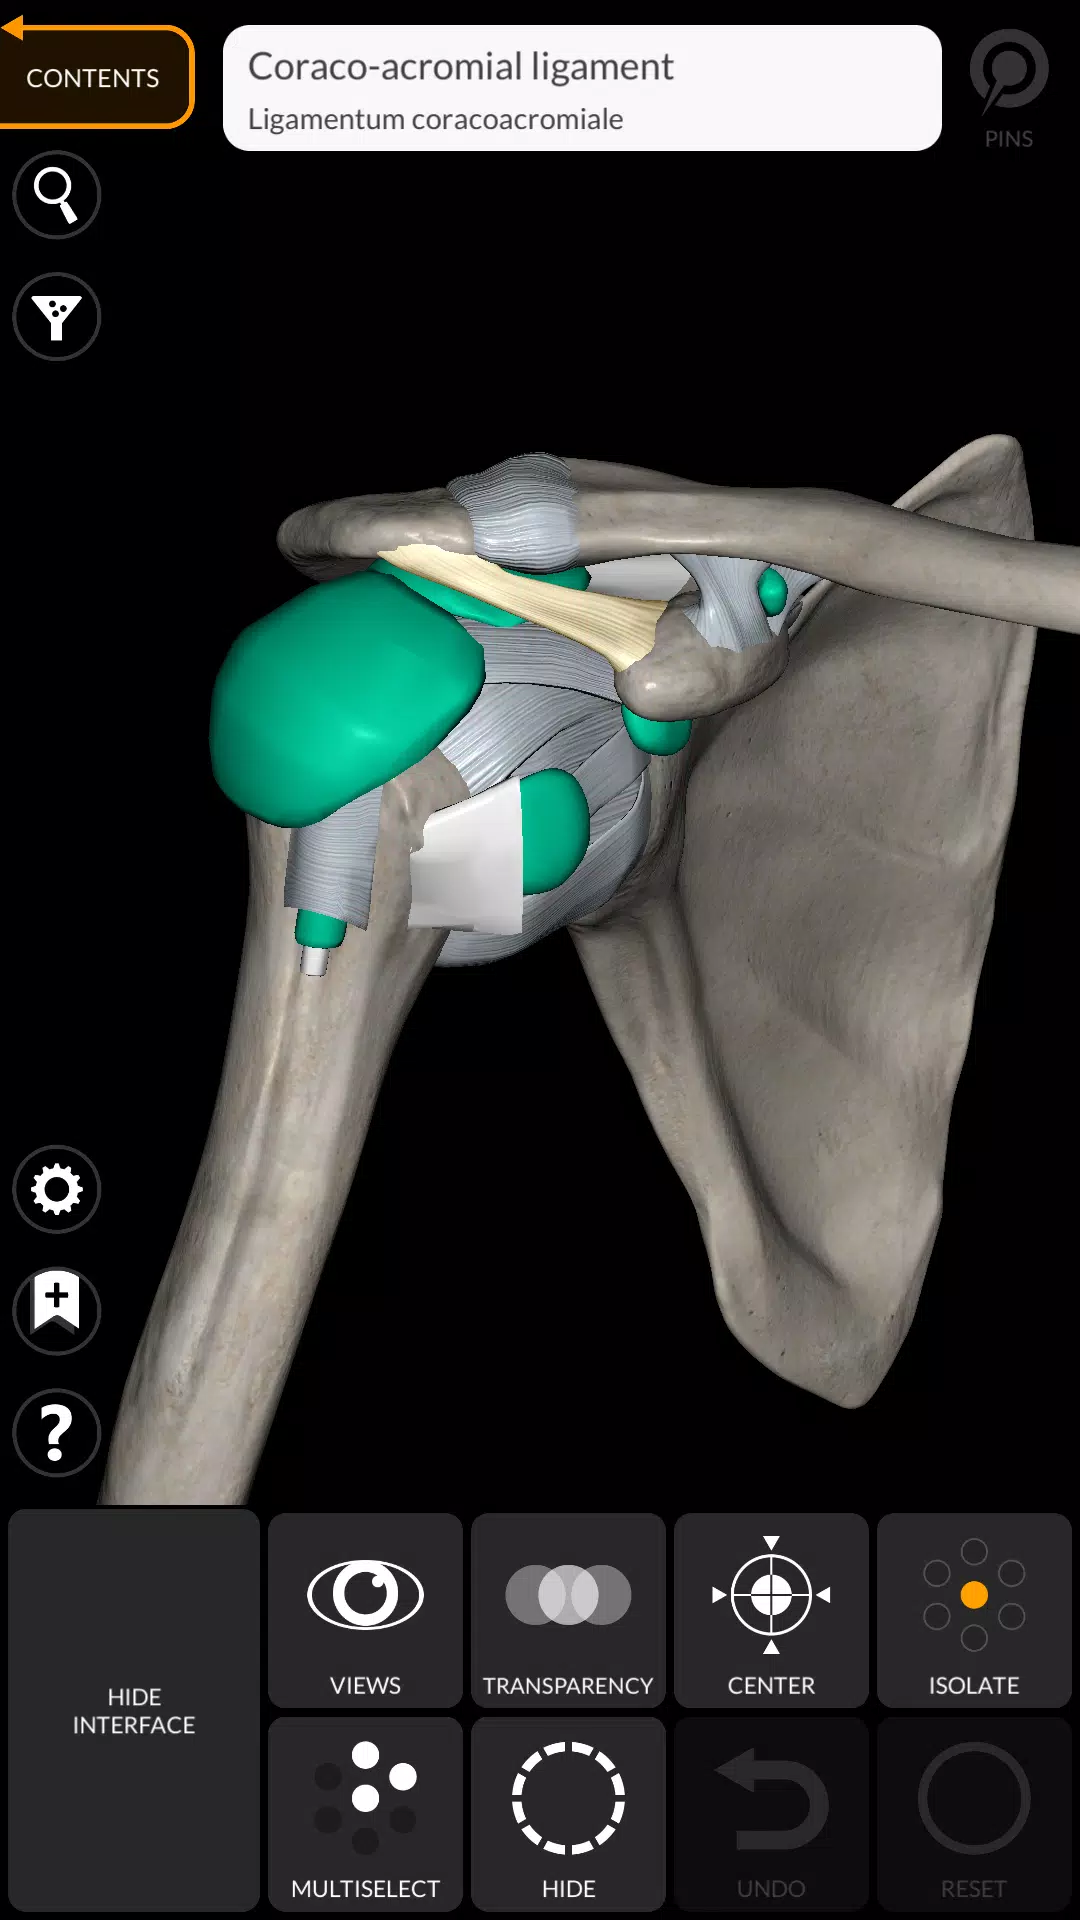

用“解剖3D地圖集”應用以引人入勝的互動方式發現人類解剖結構的複雜性。該免費下載的應用程序提供了全面的學習體驗,儘管解鎖了全部內容需要購買內置的購買。為了讓您品嚐其功能,總是可以免費訪問完整的骨骼系統和選擇其他內容,從而使您可以徹底探索該應用程序的功能。

“ Anatomy 3D Atlas”通過其用戶友好和直觀的界面徹底改變了您研究人類解剖結構的方式。您可以從任何角度檢查每個解剖結構,這要歸功於高度紋理高達4K的質地的高度詳細的3D模型。該應用程序的組織按地區和預定義的觀點簡化了對單個部分或系統組以及不同器官之間的關係的研究。

專為醫學生,醫生,物理治療師,護理人員,護士,運動培訓師以及任何渴望加深他們對人體解剖結構的理解的任何人設計,這是對傳統解剖學教科書的絕佳補充。

解剖3D模型

- 肌肉骨骼系統

特徵

- 簡單直觀的界面

- 在3D空間中旋轉並縮小每個型號

- 隱藏或隔離單個或多個選擇模型的選項

- 過濾以隱藏或顯示每個系統

- 搜索功能可以輕鬆找到每個解剖部分

- 書籤功能以保存自定義視圖

- 智能旋轉自動移動旋轉中心

- 透明度函數

- 通過從淺表層到最深的肌肉的肌肉可視化肌肉

- 通過選擇模型或引腳,相關的解剖術語顯示

- 肌肉的描述:起源,插入,神經和動作

- 顯示/隱藏UI接口(小屏幕非常有用)

Anatomy 3D Atlas應用截圖